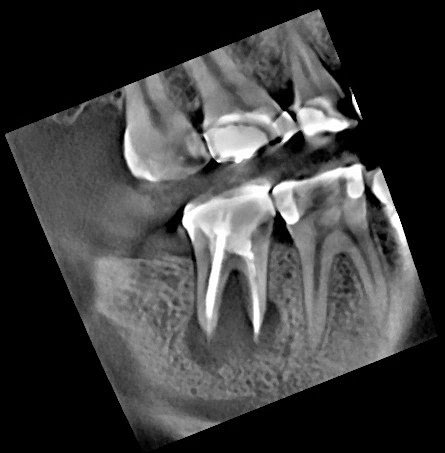

Note the bone levels around the tooth. They are identical to the pre-op bone levels. Intentional replantation has preserved the natural tooth AND the periodontium.

Previous posts have discussed the often overlooked surgical option of intentional replantation. The following case is an example of 3.5 yr success of intentional replantation of a Md second molar.

At this point, retreatment or surgery are the options to preserve the tooth. With a crown, not needing to be replaced, a long post and overfilled gutta percha – which can be difficult to retrieve, we considered a surgical approach. Since this is a second molar, the buccal bone is too thick to allow for conventional surgical approach (apicoectomy). After discussing risks of intentional replantation, pt elected to preserve tooth using intentional replantation.